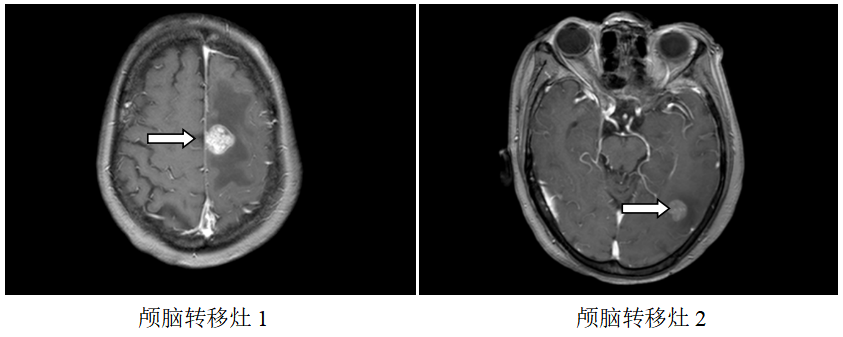

颅脑MR:左侧额、枕叶脑转移瘤;

图1.2019.7.5影像(基线评估)

诊断:食管胃交界腺癌腹腔、腹膜后、左腋窝、左锁骨区淋巴结转移脑转移(cT4aN3M1,IV期,HER2扩增,MSS,PD-L1-)